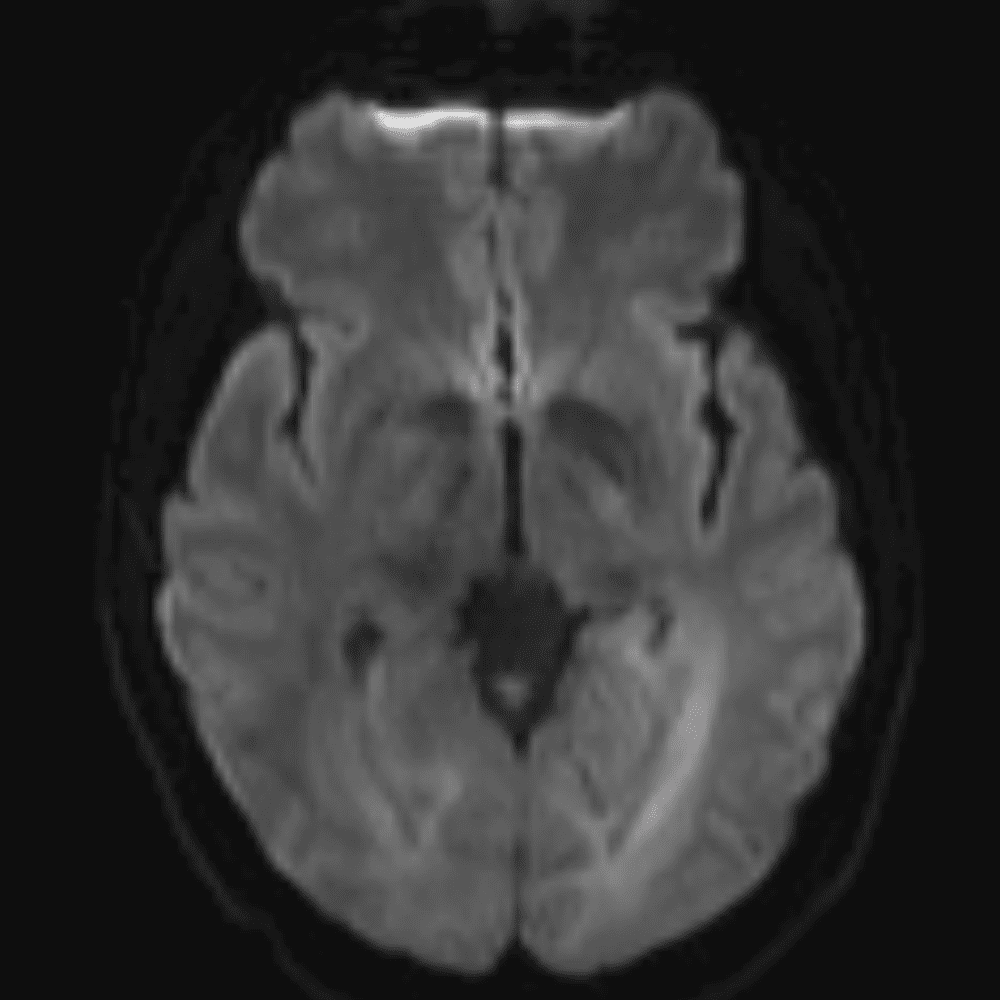

๋‹น์ง ์‹œ ํ”ํžˆ ๋ณผ ์ˆ˜ ์žˆ๋Š” ์‚ฌ๋ก€์˜ ์ „ํ˜•์ ์ธ ์˜ˆ๋ฅผ ํฌํ•จํ•ฉ๋‹ˆ๋‹ค.

39 ์‚ฌ๋ก€

์—ฐ์Šต

๋ฏธ๋ฌ˜ํ•˜๊ฑฐ๋‚˜ ์–ด๋ ค์šด ์‚ฌ๋ก€์™€ ์ผ๋ถ€ ์ •์ƒ ์‚ฌ๋ก€๋ฅผ ํฌํ•จํ•˜์—ฌ ๋‹น์ง์„ ์‹œ๋ฎฌ๋ ˆ์ด์…˜ํ•ฉ๋‹ˆ๋‹ค.

50 ์‚ฌ๋ก€